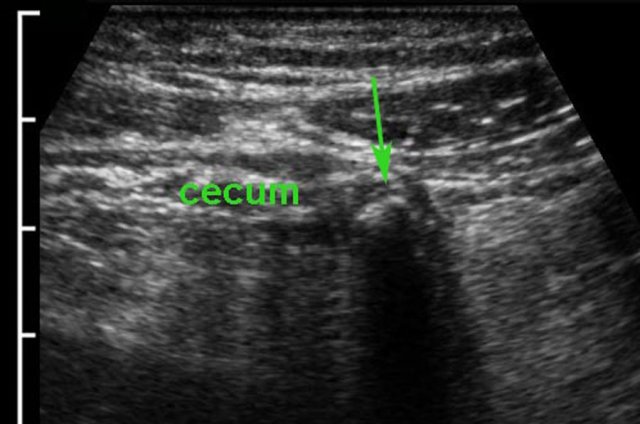

If enlarged mesenteric lymph nodes are the only US findings in a young patient with RLQ pain, the diagnosis of viral mesenteric lymphadenitis can be considered.

It is however mandatory to identify the normal appendix (arrow) with certainty, because enlarged nodes can be secondary to appendicitis.

In this patient young patient with cecal diverticulitis the most prominent fat stranding (arrowheads) is found around a cecal diverticulum, containing a fecolith (*).

The appendix (arrow) is secondarily inflamed due to the nearby cecal diverticulitis.

Complete cure with conservative treatment.